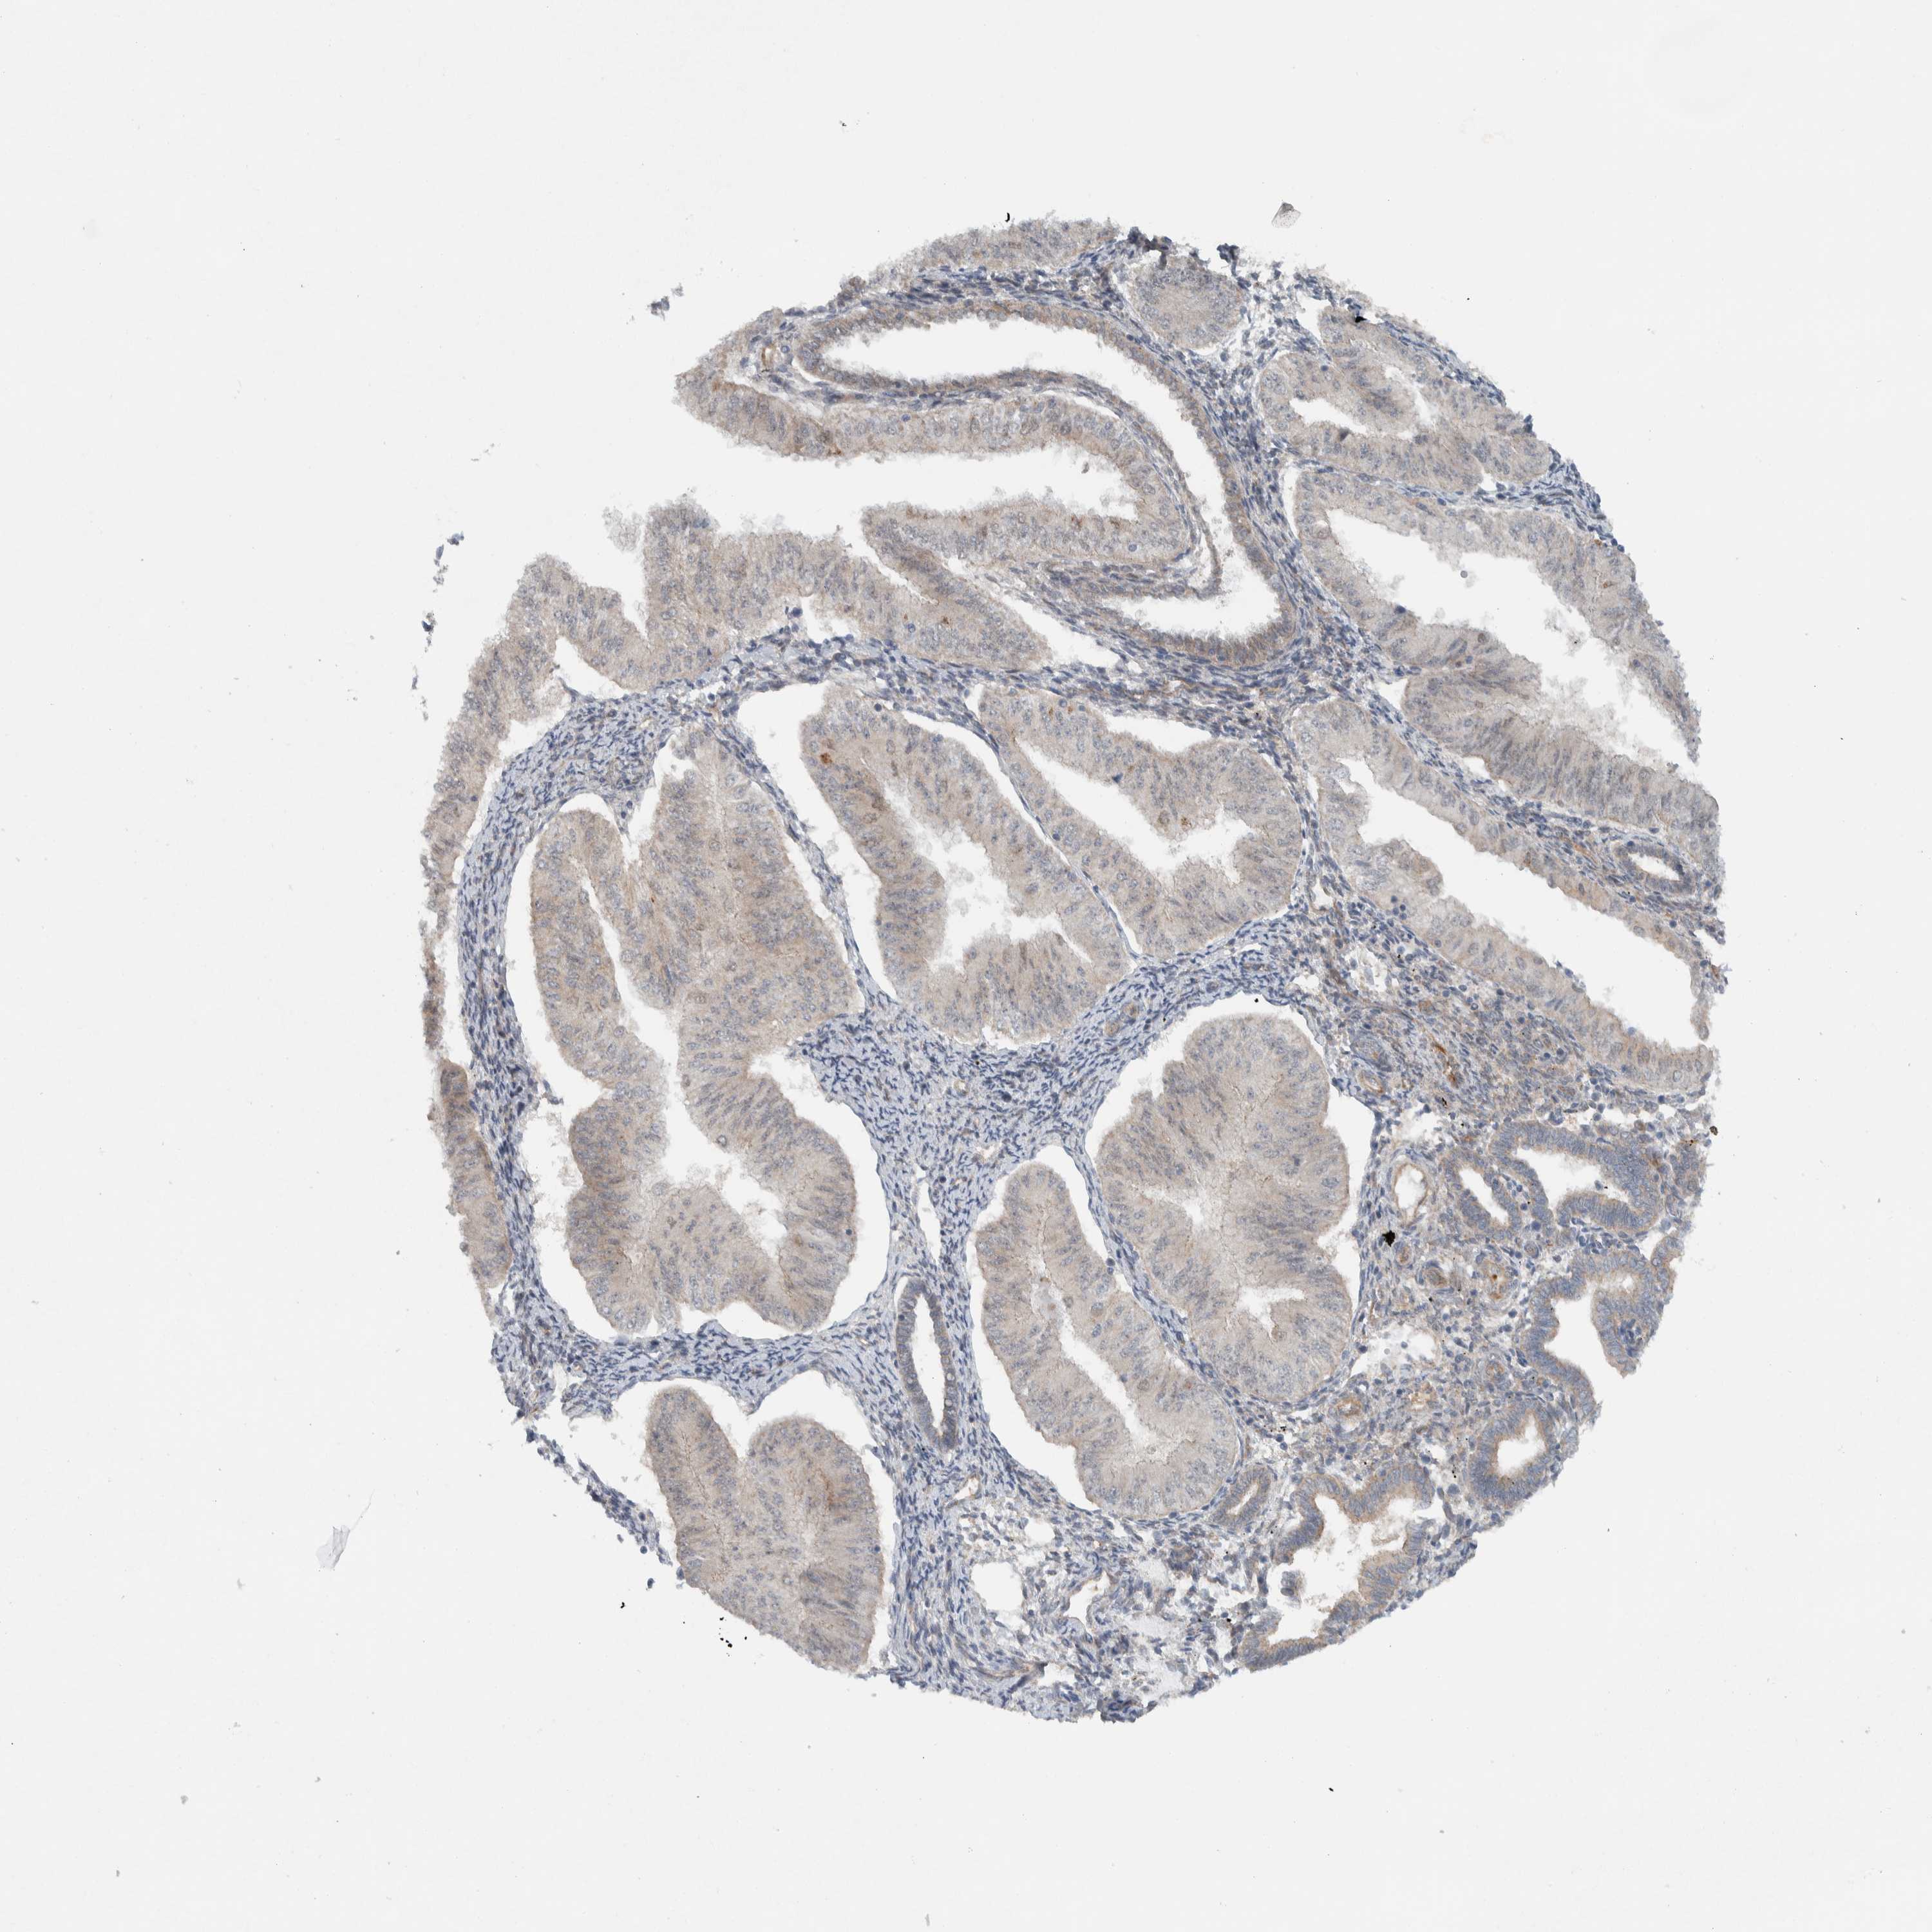

ENDOMETRIAL CANCER - Protein expressioni

A mouse-over function shows sample information and annotation data. Click on an image to view it in a full screen mode. Samples can be filtered based on level of antibody staining by selecting one or several of the following categories: high, medium, low and not detected. The assay and annotation is described here.

Note that samples used for immunohistochemistry by the Human Protein Atlas do not correspond to samples in the TCGA dataset.

Antibody stainingi

Antibody staining in the annotated cell types in the current human tissue is reported as not detected, low, medium, or high, based on conventional immunohistochemistry profiling in selected tissues. This score is based on the combination of the staining intensity and fraction of stained cells.

Each image is clickable and will lead to virtual microscopy that enables deeper exploration of all samples and also displays staining intensity scores, fraction scores and subcellular localization as well as patient and tissue information for each sample.

Antibody HPA024093

Staining

High

Medium

Low

Not detected

Intensity

Strong

Moderate

Weak

Negative

Quantity

>75%

75%-25%

<25%

None

Location

Nuclear

Cytoplasmic/membranous

Cytoplasmic/membranous,nuclear

Adenocarcinoma, NOS